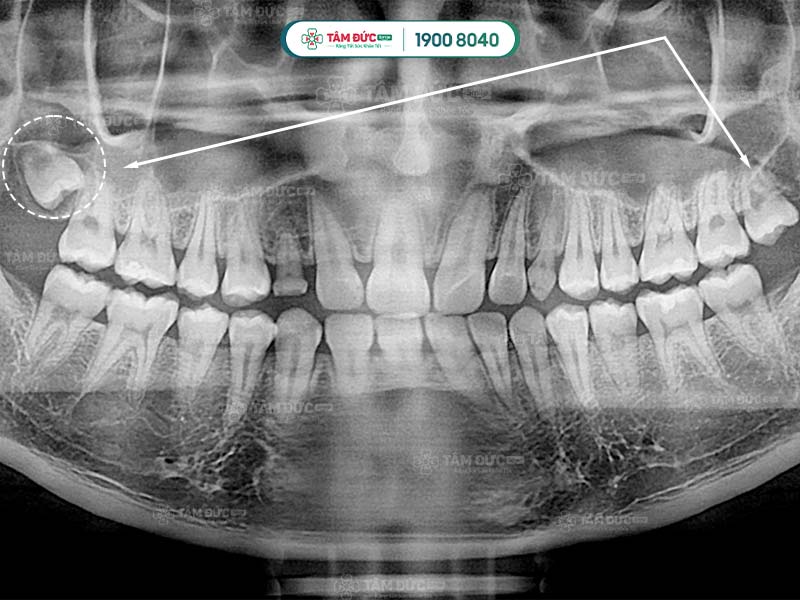

Răng khôn qua phim chụp X-Quang

Hình dạng của chân răng khôn hay còn gọi là gốc răng khôn ở mỗi người có sự khác biệt. Răng khôn có hình dáng khác với những chiếc răng còn lại, chúng hầu như có từ 2, 3 thậm chí là 4 gốc răng. Các chân này thường hợp nhất với nhau tạo thành chân lớn. Tuy nhiên, một số khác lại cuộn tròn hoặc xòe ra các hướng khác nhau.

Một số trường hợp đặc biệt, răng khôn có thể có nhiều hơn 4 chân răng. Chính vì thế, việc biết được răng khôn có mấy chân là điều cần thiết giúp bác sĩ lựa chọn giải pháp nhổ răng khôn an toàn nhất.

Đầu tiên là bước thăm khám lâm sàng để thu thập những chỉ số cần thiết như: chỉ số đông máu, số lượng tiểu cầu… Tiếp đến, Quý khách sẽ được chụp X-quang nhằm xác định răng khôn có mấy chân và hình dáng của chân răng khôn.